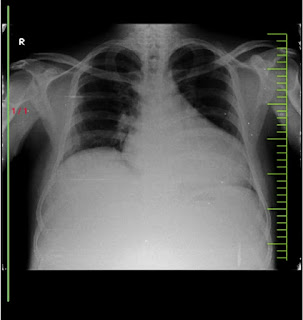

A 44 YR OLD MALE C/O B/L PEDAL OEDEMA SINCE 6 MONTHS, ABDOMINAL DISTENSION SINCE 6 MONTHS ,COUGH WITH OUT EXPECTORIATION SINCE 4 DAYS

A 44 YR OLD MALE CAME TO OPD WITH COMPLAINTS OF B/L PEDAL OEDEMA SINCE 6 MONTHS, ABDOMINAL DISTENSION SINCE 6 MONTHS ,COUGH WITH OUT EXPECTORIATION SINCE 4 DAYS

COUGH WITH OUT EXPECTORIATION SINCE 4 DAYS NO AGGREVATIMG AND RELIEVING FACTORS

RESPIRATORY SYSTEM B/L AE+